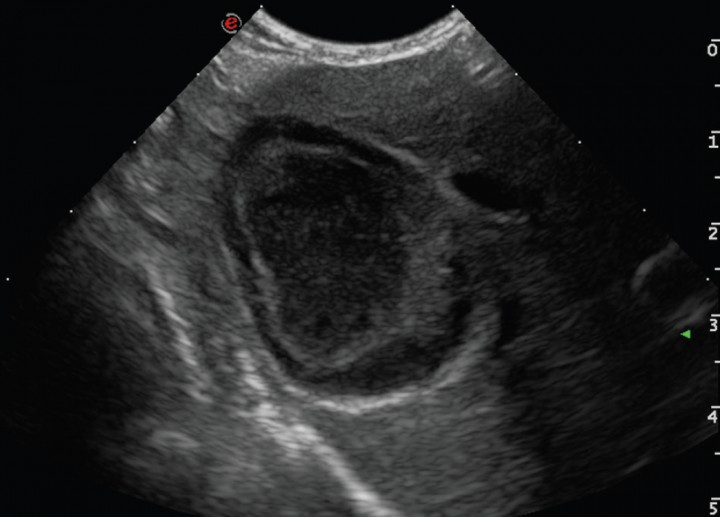

El examen ecográfico fue realizado con sondas semiconvex (3-9 MHz) o lineales (4-13 MHz) (Esaote, Mylab 70, Barcelona, España) según el tamaño del paciente; los animales se posicionaban en decúbito lateral, supino o en estación para confirmar que el contenido de la vesícula biliar era inmóvil. En el examen ecográfico se evaluó el modelo del contenido biliar, grosor de la pared (normal < 3 mm),[ Spaulding KA. Ultrasound corner: Gallbladder Wall thickness. Vet Radiol & Ultrasound 1993; 34:270-272. ] aspecto del tejido adyacente a la vesícula, ecogenicidad del hígado (normal, hiperecogénico, hipoecogénico, o heterogéneo), si existía efusión peritoneal y alteraciones ecográficas en otros órganos. El grado de distensión de la vesícula biliar se evaluó en corte longitudinal (valores de referencia: longitud 3–7,8 cm y profundidad 1,4–4,3 cm) y en corte transversal (valores de referencia: anchura 1,8–4,9 cm y profundidad 1,5–4,1 cm).[ Atalan G, Barr FJ, Holt PE: Estimation of the volumen of the gall bladder of 32 dogs from linear ultrasonographic measurements. Vet Rec, 2007;160: 118-122. [PubMed] ] El modelo del contenido de la vesícula biliar se dividió en 5 tipos (clasificación modificada de JG Besso[ Besso JG, Wrigley RH, Gliatto JM, Webster CRL: Ultrasonographic appearance and clinical fidings in 14 dogs with mucocele. Vet Radiol & Ultrasound, 2000; 41: 261-271. [PubMed] ] y J Choi[ Choi J, Kim A, Keh S, Oh J, Kim H, Yoon J. Comparison between ultrasonographic and clinical fidings in 43 dogs with gallbladder mucoceles. Vet Radiol & Ultrasound, 2014; 55:202-207. [PubMed] ]): Tipo I, sedimento ecogénico inmóvil (Fig. 1); Tipo II, patrón estriado (sedimento ecogénico inmóvil en el que se visualizan estriaciones hipoecogénicas finas y mal definidas desde el interior hacia la pared de la vesícula; Fig. 2); Tipo III, en forma de estrella (material ecogénico en el centro de la luz vesical que emite prolongaciones hipoecogénicas hacia la periferia presentando forma de estrella; Fig. 3); Tipo IV, combinación de patrón de kiwi-estrella (sedimento ecogénico ocupando la zona central de la vesícula biliar en donde se producen prolongaciones con finas estriaciones hacia la periferia; Fig. 4), Tipo V, modelo de kiwi (material ecogénico inmóvil con finas estriaciones hipoecogénicas atravesándolo y ocupando el centro de la luz vesical; Fig. 5).

<p>Imagen ecográfica de la vesícula biliar en corte transversal. Modelo de mucocele biliar de Tipo I: se observa la vesícula biliar distendida con gran cantidad de contenido ecogénico inmóvil en su interior.</p>

Figura 1

Imagen ecográfica de la vesícula biliar en corte transversal. Modelo de mucocele biliar de Tipo I: se observa la vesícula biliar distendida con gran cantidad de contenido ecogénico inmóvil en su interior.